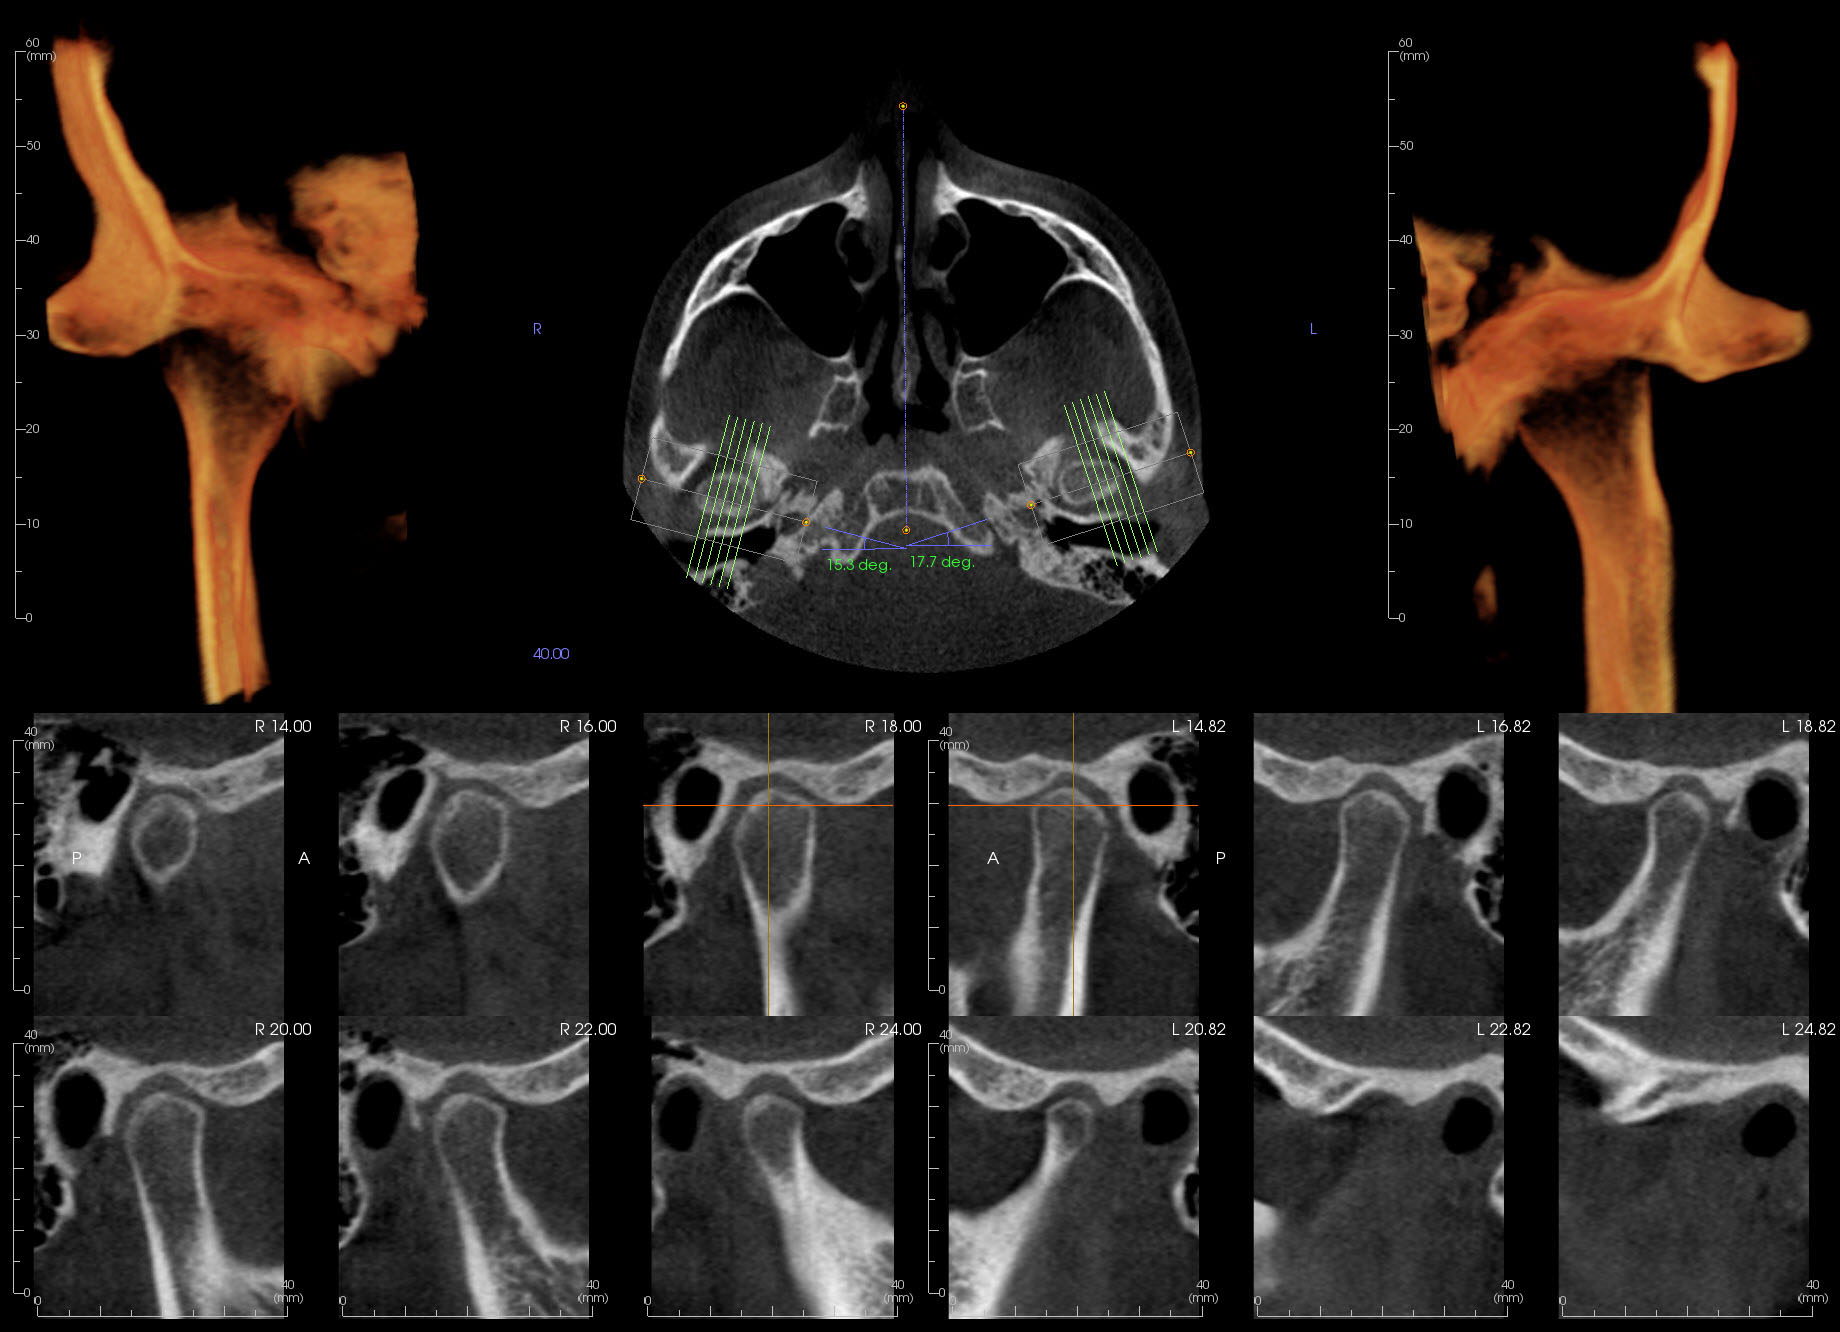

Evaluation of TMJs for Temporomandibular disorders, asymmetry and potential pathology

Implant site analysis for available bone height and width, bone quality and tracing of the IAC if posterior mandibular sites are indicated

CBCT imaging interpretation reports include comprehensive analysis of all structures within the field of view. Your clinical questions if submitted will be addressed. A thorough review of the entire scan volume will be done to rule out pathology and report any significant incidental findings. If requested, Implant survey of up to 4 implant sites is included at no additional fee. Proximity to vital anatomic structures and tracing of the Inferior alveolar canal will be done if indicated. An additional fee of $60 will apply if measurements of more than 4 implant sites is requested.

CBCT cases evaluations irrespective of FOV are $105 per case and includes general review of pathology and anatomical structures within the whole field of view(FOV) and focus on answering your clinical questions. If requested, reports also includes measurements of bone height and width for up to 4 potential implant sites and tracing of the IAC. An additional fee of $60 will be added if measurement of more than 4 implant sites is required.